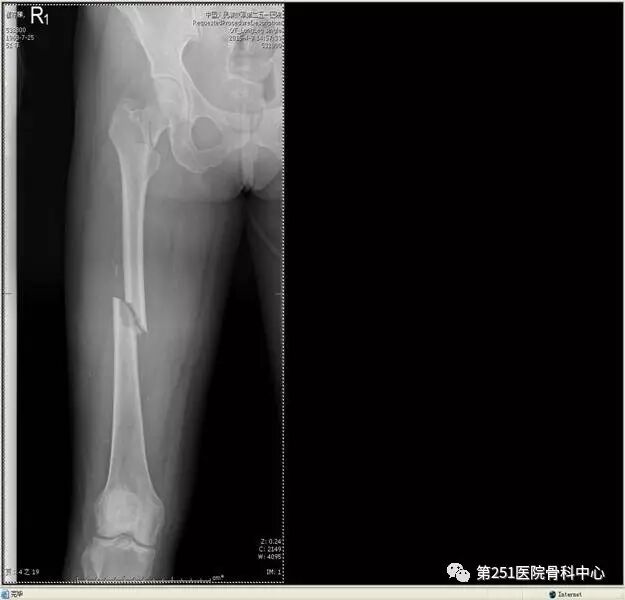

病例4:女性,车祸伤,同侧股骨、股骨颈合并胫腓骨骨折。

![]()